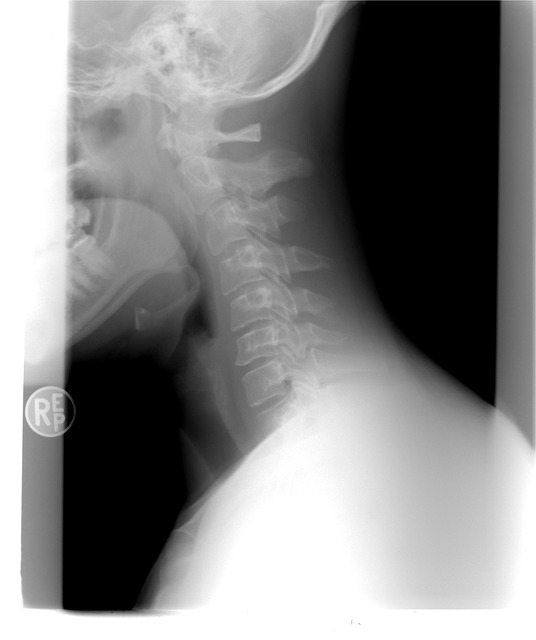

갑상선 목부음의 경고 신호, 방치하면 수술까지?

갑상선 목부음 증상

갑상선 목부음은 갑상선종으로 불리우는데요. 갑상선종의 크기가 커지거나 통증이 심해지면 숨을 쉬거나 음식을 삼키는데 불편함이 생겨 일상생활속에서 많은 불편함을 느낄 수 있습니다.

갑상선종은 종류가 많아서 구분하여 치료를 해야 합니다. 다결절 갑상선종은 가장 흔한 형태로서 여러개의 결절이 갑상선에 발견되는 증상입니다. 미만성 갑상선종은 갑상선이 전체적으로 붓는 증상입니다. 흉골 하 갑상선종은 갑상선이 흉골 뒤쪽에서 자라나는 걸로 기도나 주변 혈관을 압박하게 되고 계속 크기가 자랄 경우에는 수술이 필요합니다.